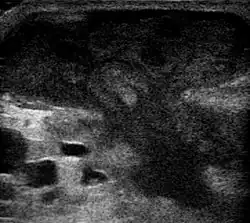

Метод выбора лечения абсцесса брюшной полости — чрескожное дренирование или пункция под контролем УЗИ.